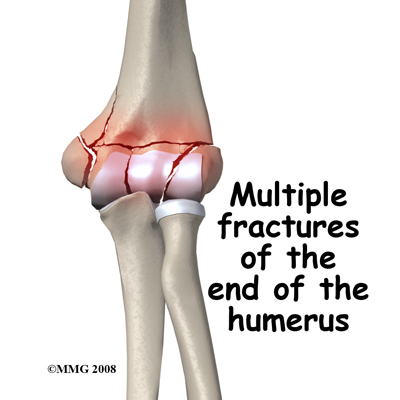

T or Y Fractures. The lower part of the humerus divides into two columns that support the joint. If you sustain a blow on the elbow, a common fracture pattern is for the columns to be broken and the fracture to extend into the trochlear region of the joint forming a T or Y pattern.

This type of injury is unstable as the columns themselves are small. Once disrupted the fracture fragments are likely to separate and leave a big gap in the joint. If possible, it is best to treat these fractures surgically (ORIF.)

Smash Fracture. More severe forces on the elbow may cause multiple fractures to the end of the humerus. The joint surface may be in many pieces and some of the bone fragments may lose their blood supply. This is a difficult situation to manage but the best results come from an ORIF surgery, restoring the joint surface, and fixing it rigidly to allow early movement of the joint.